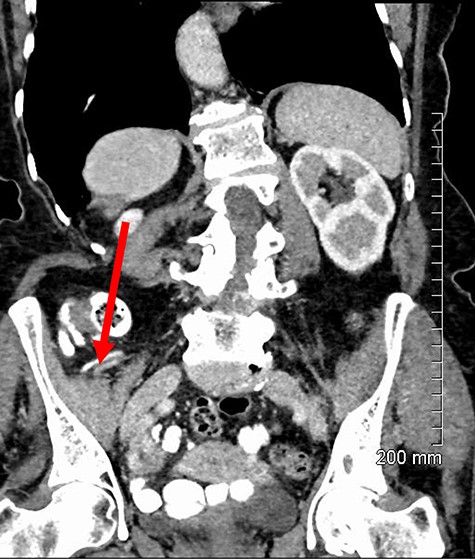

An incarcerated femoral hernia was diagnosed clinically and previous hematological investigations and imaging studies were reviewed. Full blood count, urea and electrolytes and liver function tests were within normal limits. Inflammatory markers including C-reactive protein had not been tested for preoperatively. The patient’s staging computed tomography (CT) thorax, abdomen and pelvis (performed a month before surgery) had shown fluid in the right inguinal region, appearing to lie within a small hernia (Fig. 1). A decision was made by the treating team to proceed with a joint procedure. The patient was consented for simultaneous mastectomy with axillary clearance and hernia repair.

Axial contrast-enhanced CT showing hernial sac containing fat and simple fluid but no appendix (red arrow).